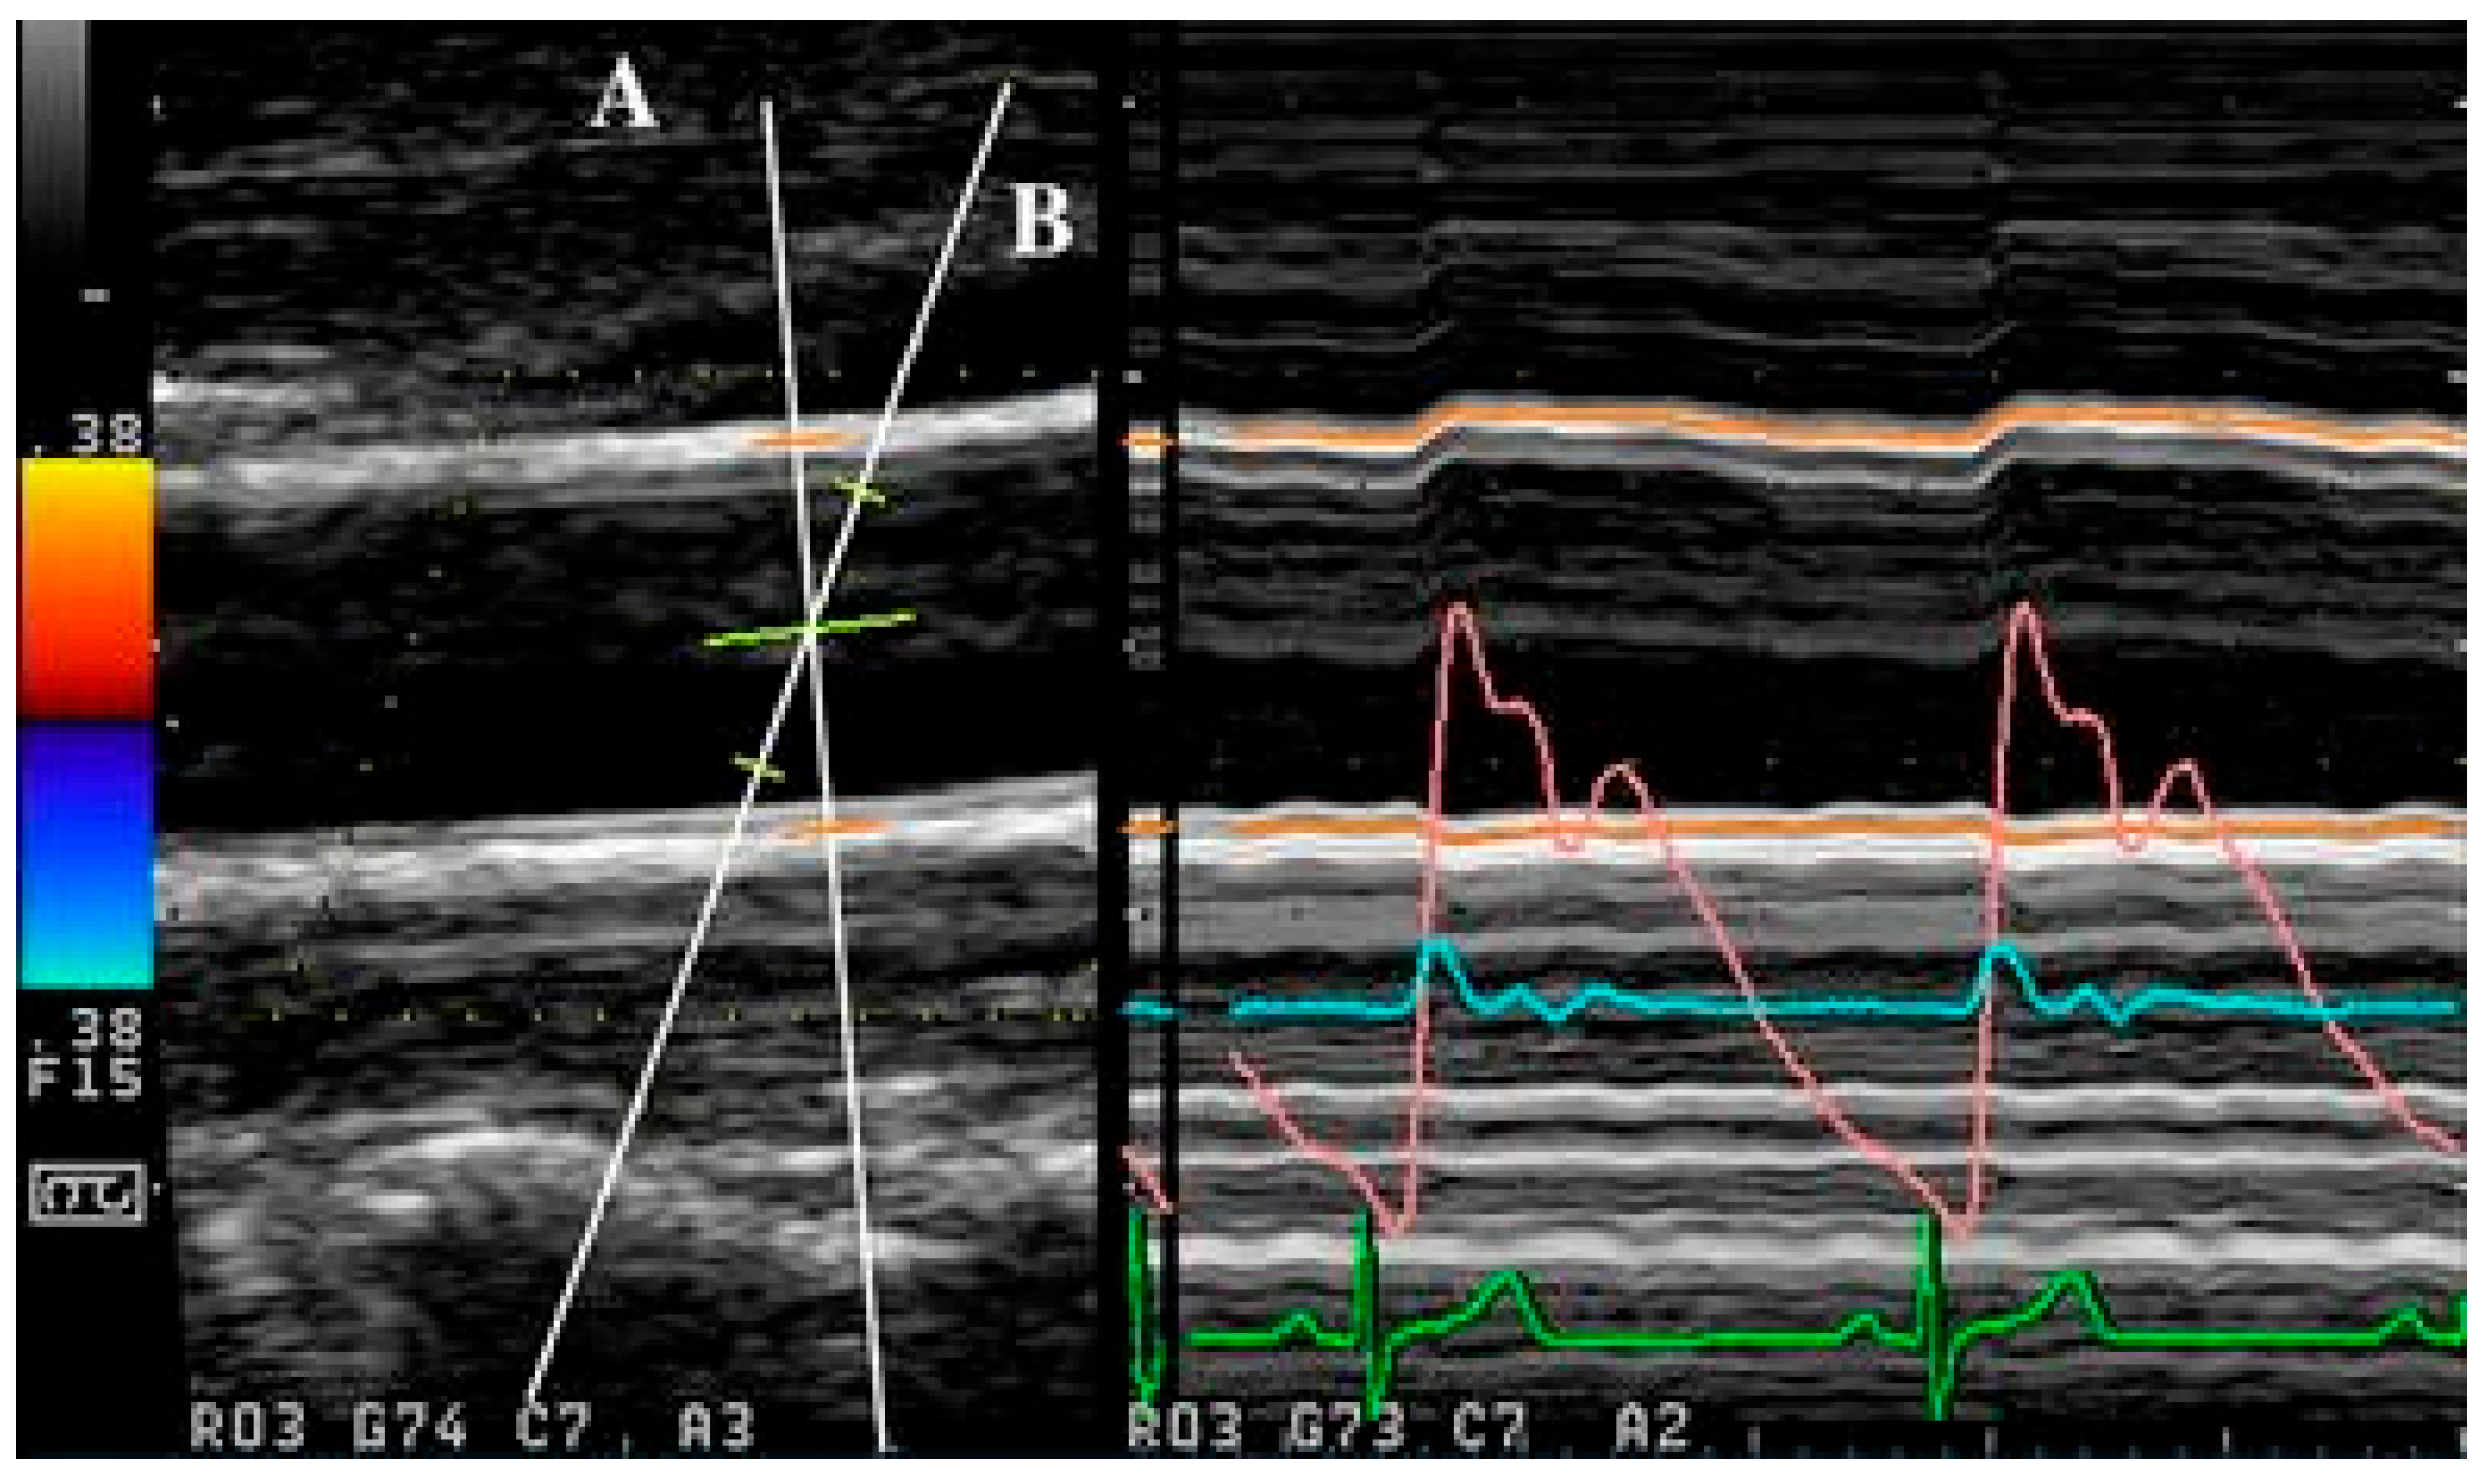

Apart from the use of singular ultrasound beams, as with the abovementioned methods, simultaneous acquisition can also be achieved with the use of multiple ultrasound beams, as demonstrated in [155,156]. In multiple beam acquisition, colour Doppler is used to obtain the blood flow velocity while diameter changes were measured using M-mode. The system consists of both the colour Doppler system and an echo-tracking subsystem that can use different ultrasound beams for velocity and diameter change, respectively. These beams can be independently manipulated, with an intersection between the beams at the range gate for both diameter and velocity measurement, as shown in Figure 4 [156]. From [155], this method was found to have low variabilities in the maximum velocity and arterial diameter measurements despite the need to manipulate different beams, which thereby supports its reproducibility.

In general, while simultaneous acquisition was more computationally complex, the advantage and limitations of each method varied. Of the discussed methods, the cross-correlation-based methods have a unique advantage in their ability to perform measurements with the use of B-mode imaging, which means that the transducer is kept in one position throughout acquisition. This ensures that the imaged region is constant, thereby preventing errors that may arise from Doppler angle adjustment. However, this method is computationally intense and may not be used in regions of excessively high velocities due to the limitations of the ultrasound system, which can be problematic for clinical use [5]. In contrast, while the dual ultrasound beam method required positioning of two beams, the results had good reproducibility [155,156]. Additionally, the ability to independently manipulate the beams may allow for flexibility in conducting measurement.